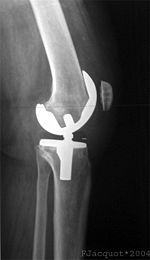

جراحة إستبدال الركبة يمكن أن تكون إستبدالا جزئياً أو إستبدال الركبة بالكامل.[2] في الإستبدال بصفة عامة تتكون من جراحة استبدال الأسطح المريضة أو التالفة للركبة بأجزاء معدنية أو بلاستيكية على شكل مكونات تسمح باستمرار حركة الركبة.

من خلال الجراحة يتم استئصال أسطح المفصل المصاب واستبدالها بمفصل صناعي. ويمكن أن تؤدي هذه الجراحة إلى تخفيف الألم وتحسين الحركة في مفصل الركبة.

لاحقا، يتم تعديل أسطح المفصل بحيث تستطيع احتواء المفصل الاصطناعي المركب من البلاستيك والمعدن. يتم الصاق المفصل الاصطناعي بعظمة الفخذ، الساق والرضفة، بواسطة مادة ملاطية أو مادة أخرى، تستعمل كمادة لاصقة فسيولوجية. من ثم، يتم تثبيت المفصل الاصطناعي إلى عضلات الركبة والأربطة الداعمة للمفصل، من أجل الحصول على أداء حركي في المفصل بشكل مماثل للوضع الطبيعي. يتكون الجزء الملتصق بعظمة الفخذ من معدن صلب وأملس، والذي يستطيع تحمل أوزان ثقيلة. يتم تغطية المفصل بضمادة مرنة.

شرح توضيحي لجراحة استبدال الركبة.